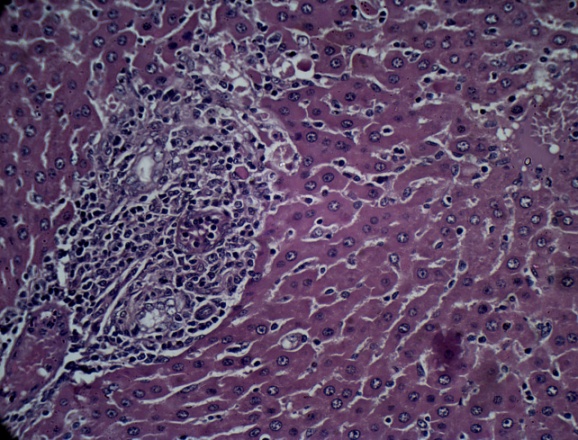

Histopathology

Histological profile of the normal control group revealed normal histology of liver with central vein, hepatocytes and portal triads. MTX induced group revealed marked degree of centrilobular necrosis along with polymorphonuclear cells infiltration, severe vacuolations in the hepatocytes and sinusoidal congestion. Pre-treatment with LIV-52 reduced MTX induced microscopic changs and showed marked beneficial effects in the liver architecture. Ambrex treatment at the low dose showed moderate degree of necrosis, mild degree of vacuolations in the hepatocytes with minimal sinusoidal congestion. Ambrex administration at high dose revealed regeneration of hepatocytes to normal architecture, absence of sinusoidal congestion and vacuolations in the hepatocytes. On the basis of the above observation, it is concluded that pre-treatment with Ambrex at high dose (500 mg/kg b. wt. p. o) have hepatoprotective activity against MTX induced hepatotoxicity (fig. 4).

A B

C D

E

Fig. 4: Representative photograph showing the effect of Ambrex on MTX induced mice liver-H & E stain X400 magnification. (A) Normal control, (B) Positive control (C) MTX+LIV 52, (D) MTX+Ambrex (250 mg/kg b. wt., p. o.) and (E) MTX+Ambrex (500 mg/kg b. wt., p. o.) treated group